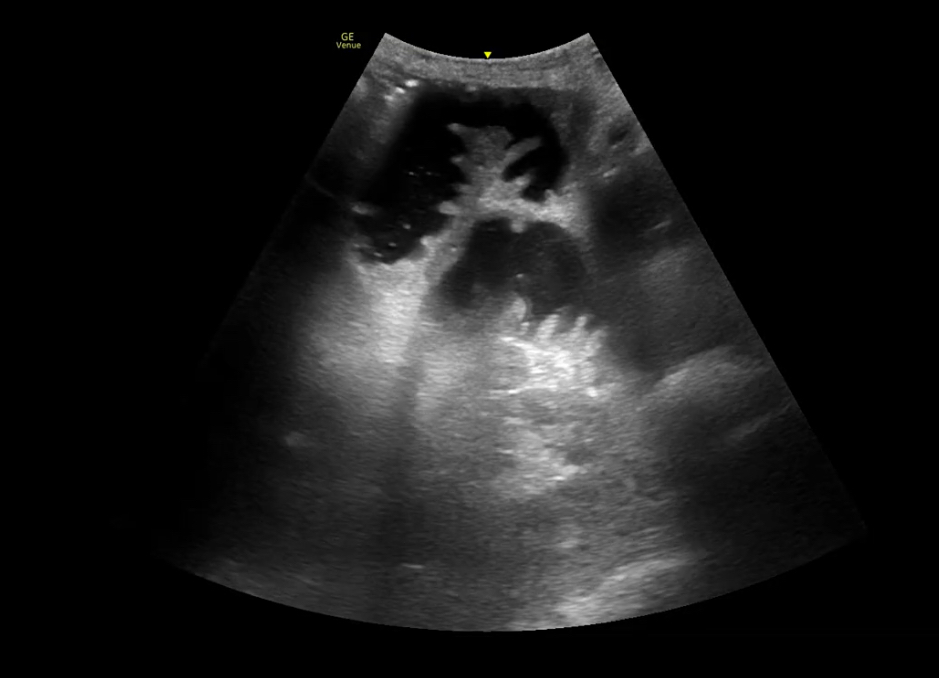

Ante AP de cirugía, dolor abdominal y vómitos, se realiza rx abdominal que resulta normal. Dada la alta sospecha, se realiza ecografía: gran cámara gástrica con contenido en su interior con dinámica «en lámpara de lava». Además, asas de intestino delgado dilatadas (diámetro 2,9 cm) con movimiento de peristalsis y rebote y edema de pared. Compatible con obstrucción intestino delgado.